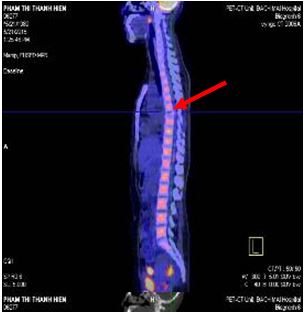

- Chụp PET/ CT sau 1 chu kỳ hóa chất

Tổn thương xẹp đốt sống D7 không hấp thu FDG

Tổn thương cung trước xương sườn VI tăng hấp thu FDG, max SUV: 4.23

Hình 6: Hình ảnh PET/CT sau một chu kỳ hóa chất: Tổn thương xẹp đốt sống D7 không hấp thu FDG (mũi tên đỏ), tổn thương cung trước xương sườn VI (mũi tên trắng)

Bệnh nhân được chụp PET/CT đánh giá sau điều trị: Không thấy hình ảnh tăng hấp thu FDG bất thường.

Hình 9: Hình ảnh PET/CT đánh giá sau điều trị: Không thấy hình ảnh tăng hấp thu FDG bất thường trên cơ thể.